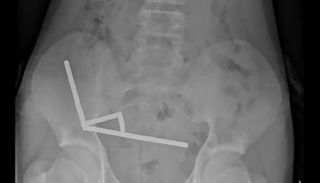

وبيّن الفريق الطبي أن هذه القطع تنتمي إلى نوع من المغناطيسات الصغيرة المحظورة في نيوزيلندا منذ عام 2013، وقد تم شراؤها من خلال منصة «تيمو». وأظهرت الأشعة أن المغناطيسات التصقت داخل الأمعاء مكوّنة أربع سلاسل متصلة، ما أدى إلى التصاق أجزاء من الأمعاء الدقيقة والغليظة وتلف في أنسجتها نتيجة الضغط المغناطيسي المستمر.